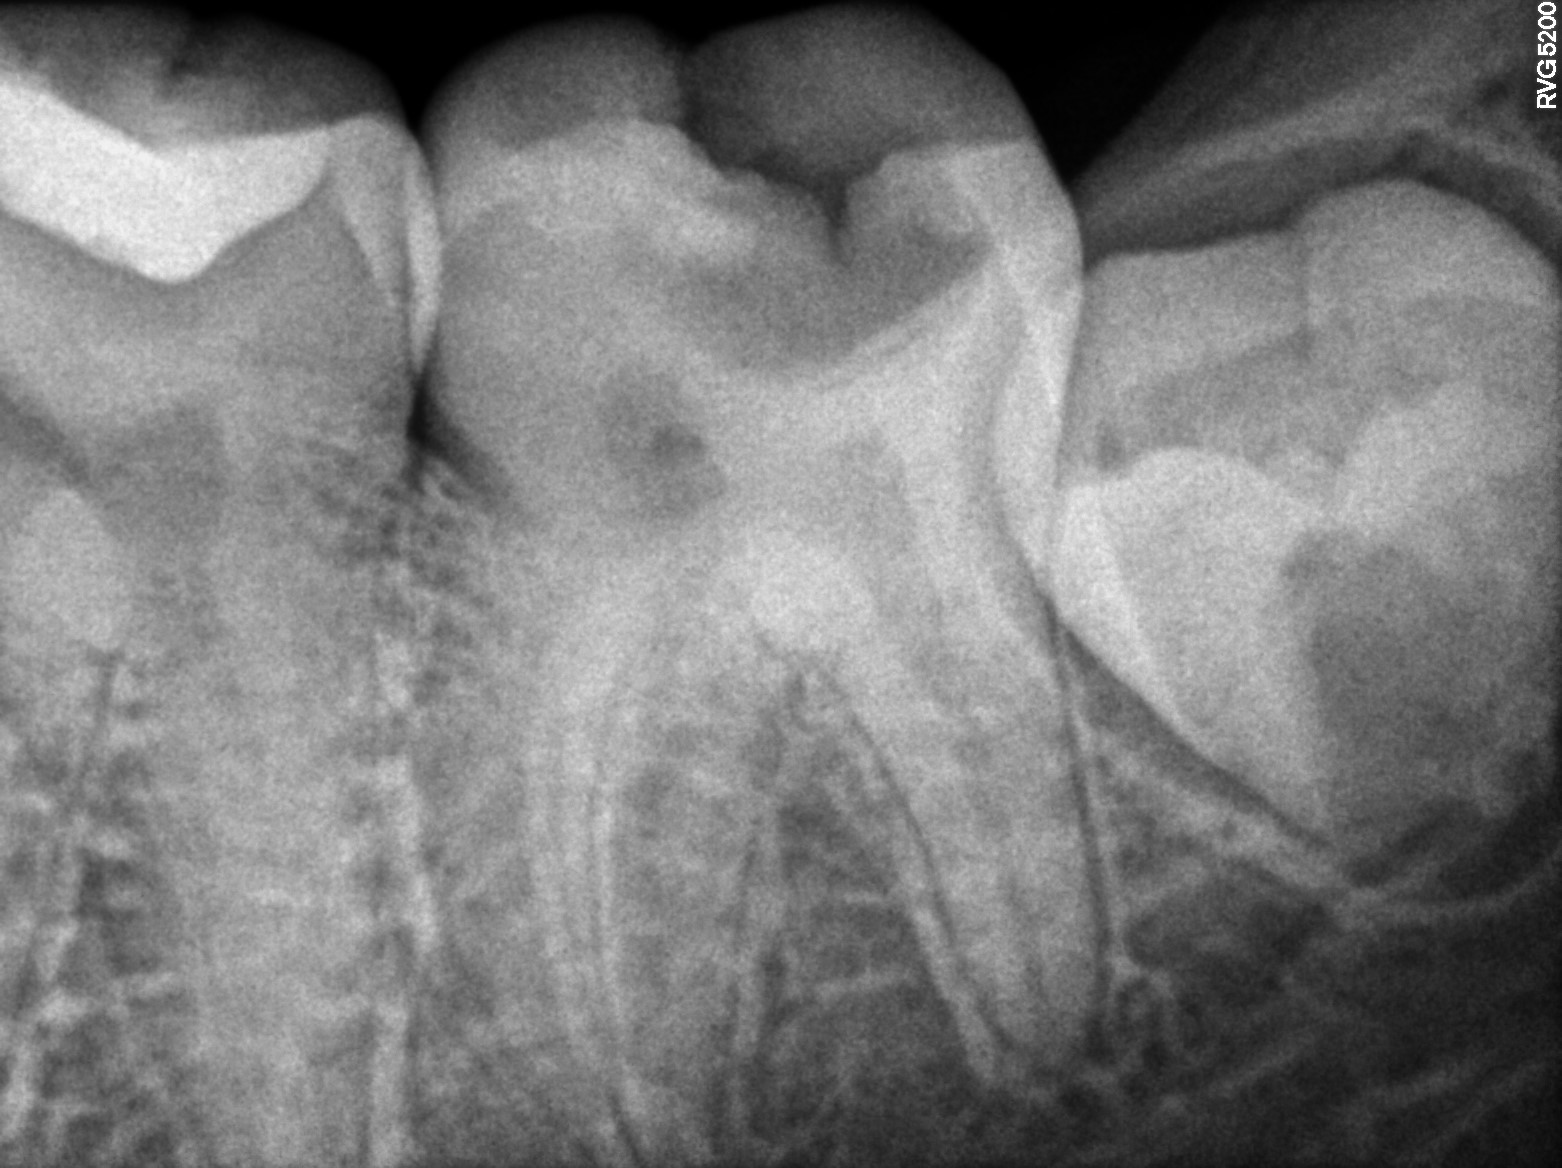

Dental Radiographs FHIR: DocumentReference · LOINC 24641-7

R5.3.jpg

24641-7

R53.jpg

R64.jpg

R54.jpg

R62.jpg